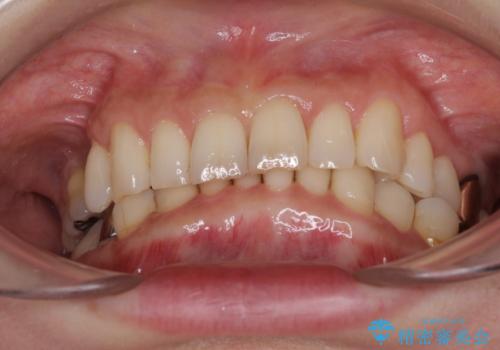

デコボコの歯とむし歯 インビザライン矯正治療とむし歯治療

- 奥歯が咬めないくらいに痛いとのことで来院された患者様です。

痛みの強い歯は、歯髄組織が強い炎症を起こしており、神経を取り除く必要であったため、速やかに根管治療を行いました。

その後、オールセラミッククラウンにて補綴治療を行う予定でしたが、処置した歯以外にも治療が必要と思われる歯があったり、デコボコした歯列も気になるとのことで、患者様希望によりインビザラインにてマウスピース矯正を行うこととしました。

まずは矯正治療前に必要なむし歯処置を行い、その後矯正治療を行ってから、最後にオールセラミッククラウンなどで補綴治療を行うこととしました。